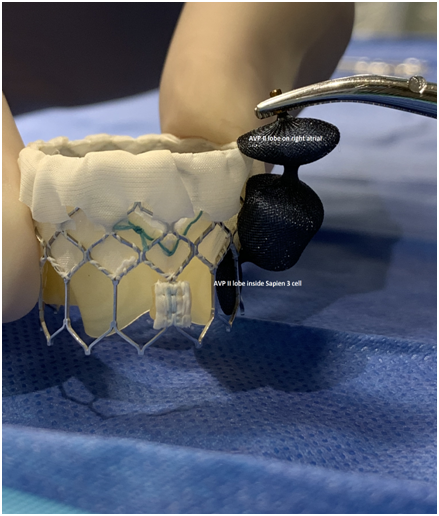

A 73-year-old female with mechanical mitral valve, tricuspid annuloplasty (32mm Edwards Physio Tricuspid incomplete ring) underwent Transcatheter Tricuspid Valve Replacement (TTVR) using off-label 29mm Edwards Sapien 3 (S3) Transcatheter Heart Valve (THV). Immediate post valve deployment, mild Perivalvular Leak (PVL) was noticed at the septal aspect (area of incomplete annuloplasty ring). Eighteen months later, patient presented with recurrent right heart failure and paracentesis due to severe tricuspid PVL (Figure 1A-C, Video 1). Percutaneous PVL closure under general anesthesia, Trans-esophageal Echocardiography (TEE) was performed. Via femoral venous access, defect was easily crossed with Agilis steerable sheath, multipurpose catheter and 0.035” glide wire. Despite recurrent attempts, wire came through the PVL but then traversed through open cells of S3 into the right ventricle (Figure 2A), confirmed with Armada 6mm balloon waist at the S3 cage (Figure 2B) (despite inflating 28mm Z med balloon inside S3 cage, Figure 2C). We decided to partially deploy the plug and assess valve function. Using 7.5F Asahi Eaucath multipurpose guide, a 12mm AmplatzerTM Vascular plug II (AVP II) was advanced through the defect. The ventricular disc was opened inside the S3 cage while body in the PVL defect (outside the S3 cage) and atrial disc on the atrial side of PVL (Figure 3A-B). With S3 function unaffected, no central leak and minimal gradient, PVL reduced to mild severity (Figure 4A-D, Video 2); the AVP II was successfully deployed (Figure 5). At 3-month follow up, there was an excellent symptomatic improvement (NYHA functional class I), with no heart failure re-hospitalization or paracentesis. Deployment of plug disc inside the valve frame is not recommended due to fear of interference with leaflet function and possible injury in long term. There was no immediate issue with the valve function in this case (due to space between the leaflet and frame of S3 and depends on size of plug used). Valve-in-Valve (S3-in-S3) would have certainly sealed all open cells treating this PVL but is more expensive option.

Figure 5 Amplatzer vascular plug II (AVP II) position in relation to Sapien 3 valve.